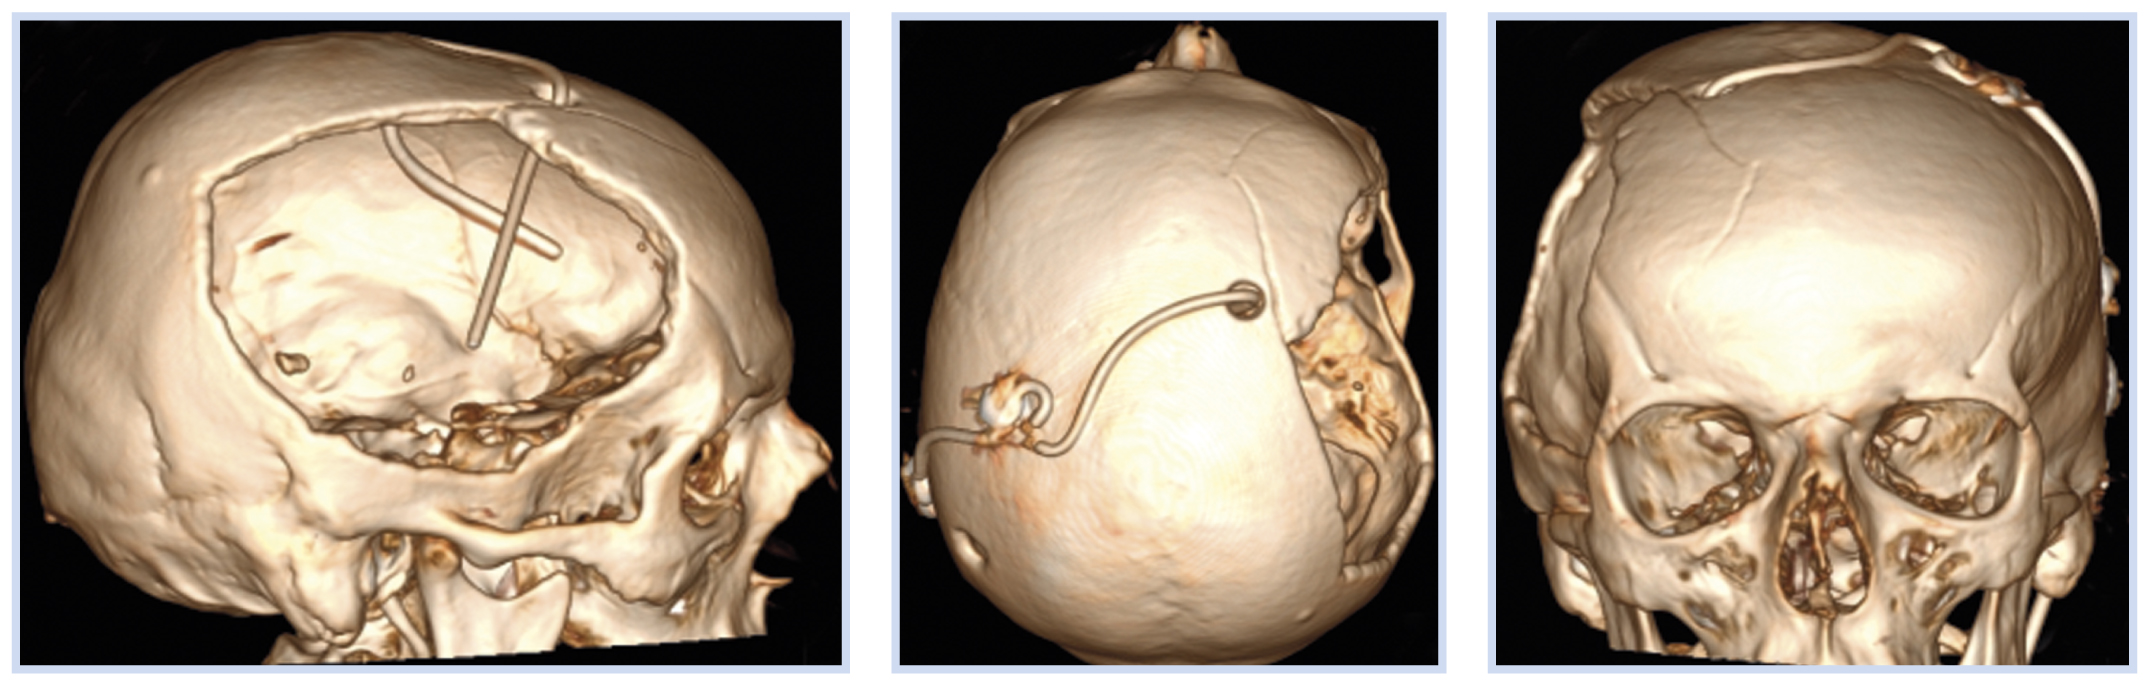

Учитывая наличие у пациента вентрикуло-перитонеального шунта, для диагностики синдрома избыточного дренирования цереброспинальной жидкости пациент был повторно осмотрен нейрохирургом: данных за дисфункцию шунтирующей системы не получено. Давление сброса клапана шунта 11 см вод. ст. Указанная симптоматика в виде икоты может иметь соматический генез или быть обусловлена влиянием атмосферного давления на вещество мозга в области посттрепанационного дефекта костей свода черепа. Гипердренирование в данном случае было маловероятно, так как в составе шунтирующей системы имеется гравитационный клапан SA (рис. 4), который повышает давление сброса ликвора при вертикализации пациента.

Рис. 4. Пациент К., 50 лет, с посттравматической гидроцефалией и посттрепанационным дефектом костей свода черепа: данные краниографии

Примечание. На краниографическом изображении (А) видны компоненты шунтирующей системы и схематичные изображения регулируемого клапана ProGAV (Б) и гравитационного клапана SA (В).